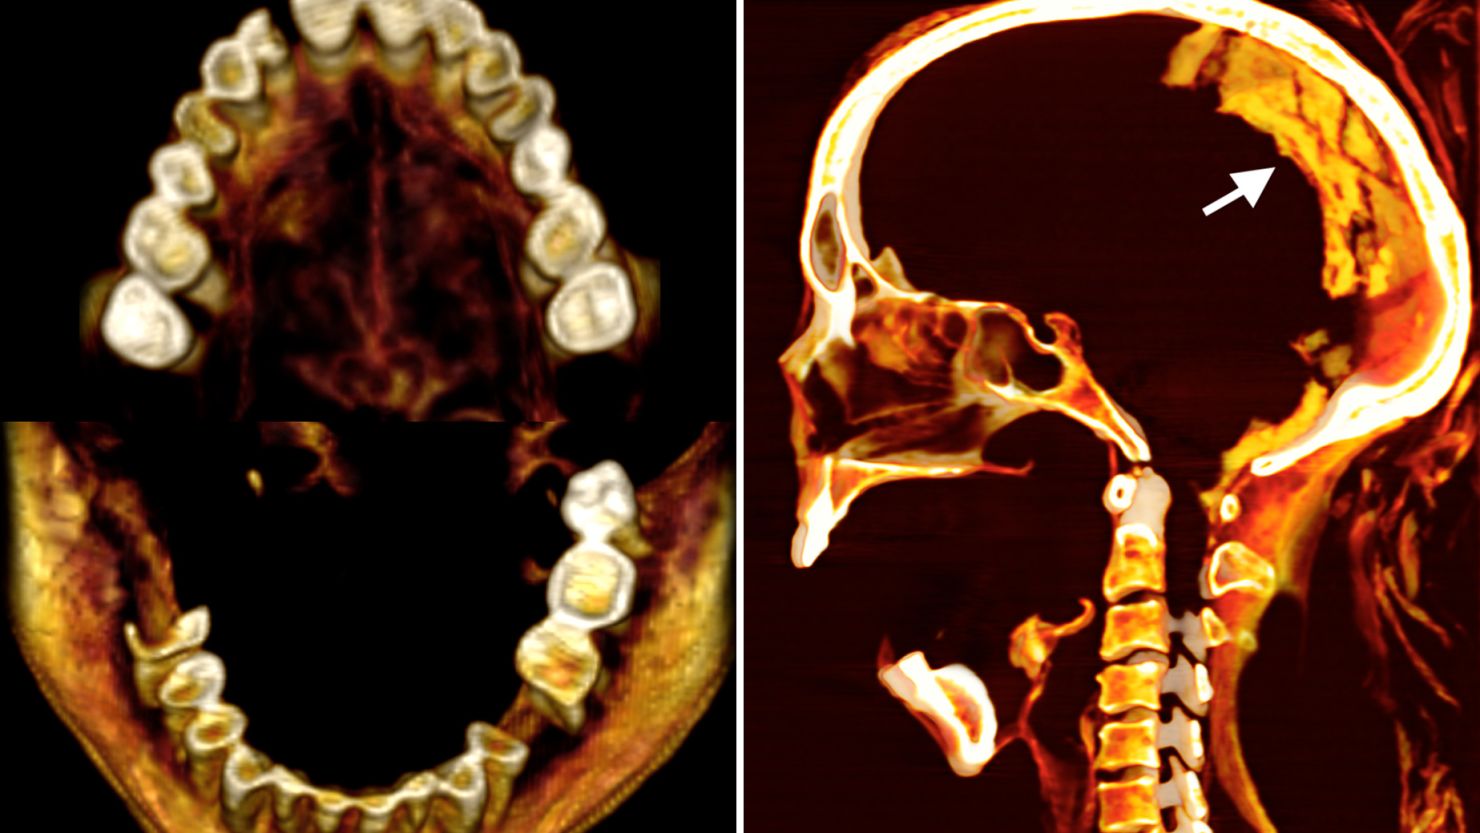

Aiming to solve the mystery, Sahar Saleem, a professor of radiology at Kasr Al Ainy Hospital at Cairo University, used CT scans to reveal details about the woman’s morphology, health conditions and preservation. Infrared imaging and other advanced techniques also helped shed more light on her life.

The woman was 48 years old when she died, and curiously her organs were still in the body contrary to typical funerary rites, Saleem found. While Saleem couldn’t determine an exact cause of death, the information she gathered led to a grisly hypothesis.